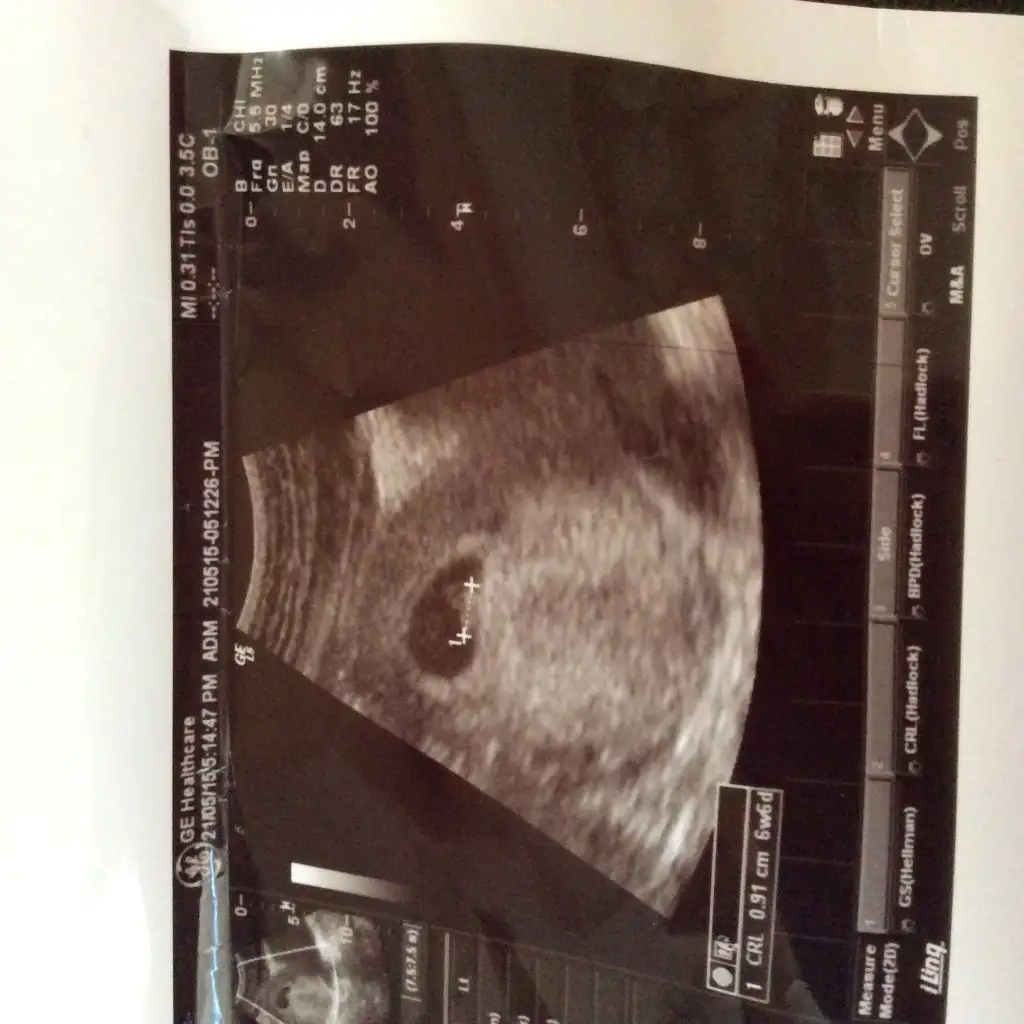

ctesi 5+4 olan bebisimin kesesi tam gununde buyuklugundeydi. Bugun başka bir doktora gittim 6+2 deyim gunune gore kese az buyumus dedi. Ama bebek nokta kadar ve yolk sac olusmus gorduk. Kese az gelismesi neden olabilir sizde olan var mi?

gecen hafta keseboyutu tarih ile tam uyumluydu. bu hafta küçük cikti yani 1haftada gelişmesi gerekenden az gelismis ama bu sırada bebek olusmus bende anlamadım ptesi belliolur inşallah sıkıntı yoktur